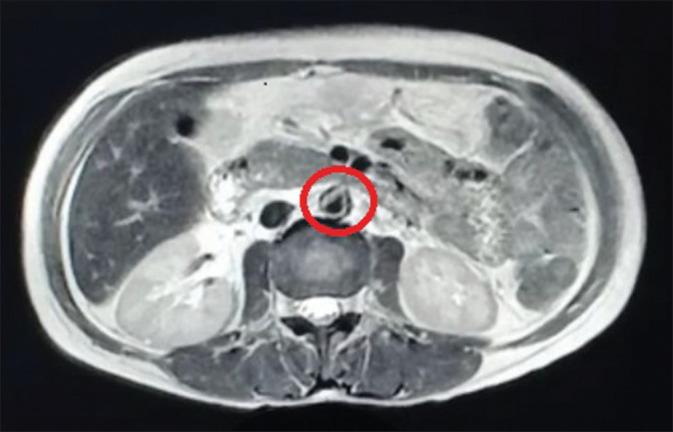

Systemic lupus erythematosus (SLE) is an autoimmune disease that can involve multiple organ systems. The most common form of vasculitis seen in SLE is small vessel vasculitis. Aortitis in SLE or antiphospholipid syndrome is an extremely rare complication. Here, we present a 32-year-old female who presented with a history of prolonged abdominal pain, who was evaluated and diagnosed to have aortitis as an unusual involvement in SLE with secondary antiphospholipid antibody syndrome.

系统性红斑狼疮(SLE)是一种可累及多个器官系统的自身免疫性疾病。SLE中最常见的血管炎形式是小血管炎。SLE或抗磷脂综合征中的主动脉炎是一种极其罕见的并发症。在此,我们报告一名32岁女性,她有长期腹痛病史,经评估被诊断为主动脉炎,这是SLE伴继发性抗磷脂抗体综合征的一种不寻常累及情况。